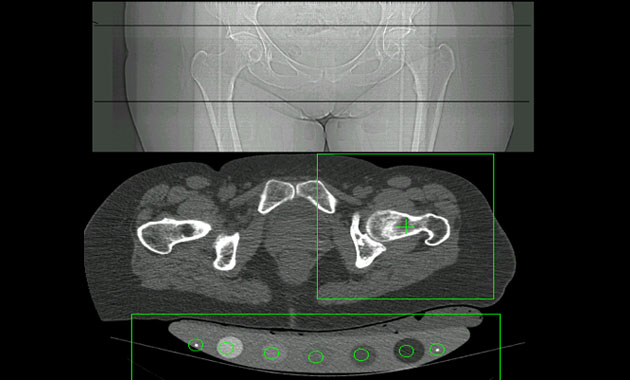

Pioneered at UCSF, quantitative computed tomography (QCT) is a test to measure bone mineral density (BMD). It is performed using a computed tomography (CT) scanner and results in a 3D image. Hip and lumbar spine are the most common choices for evaluation with QCT.